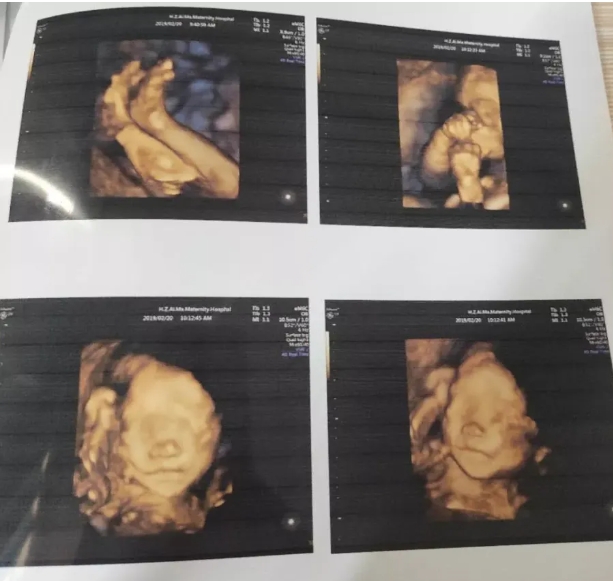

胎儿心脏彩超是胎儿心脏产前超声初步检查,主要采用超声成像技术及彩色多普勒血流成像技术,观察胎儿心脏的大体形态结构,以便对大部分胎儿先天性心血管结构畸形进行可靠的产前筛查和评估。

目前,妇产科超声学会已对产前心脏畸形的超声筛查作了规范基本项目包括:心脏位置、心率、心律、四腔心观、左室流出道及右室流出道。而针对高危胎儿的心脏彩超,在上述检查内容上再增加三血管平面,主动脉弓及导管弓平面等,可对心脏畸形做到早发现、早诊断、早治疗。